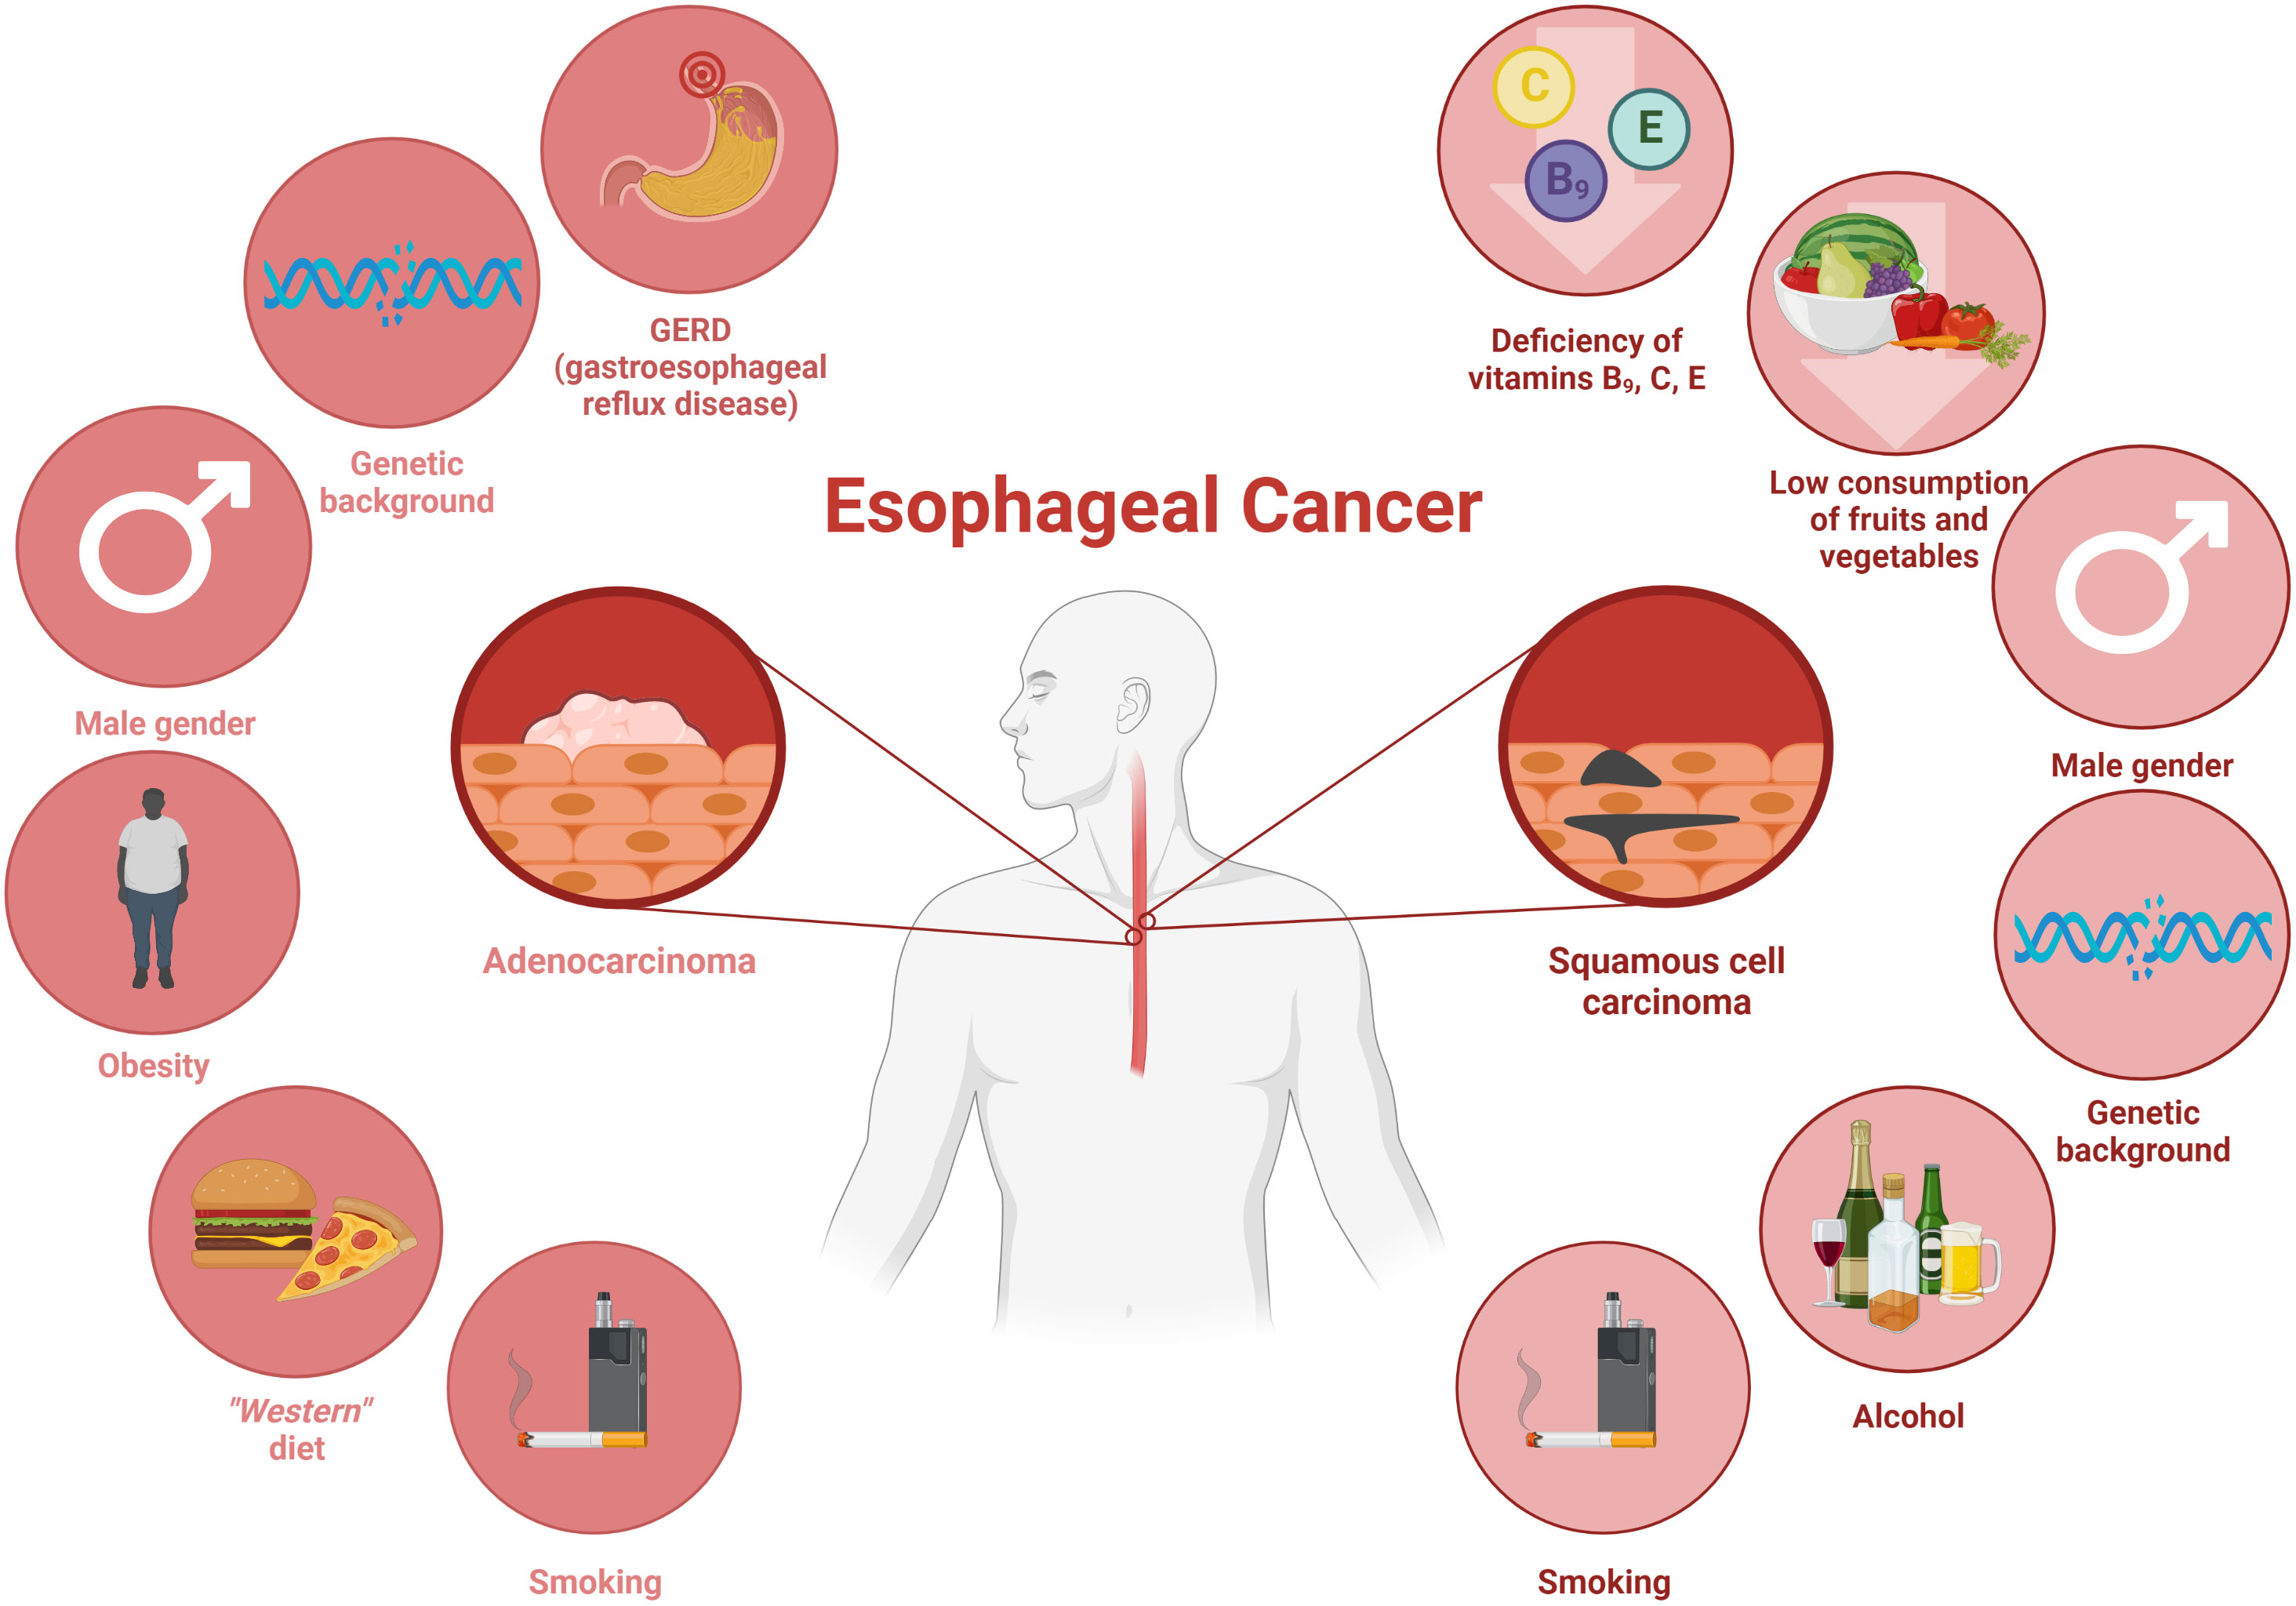

Esophageal Cancer Age Range Screening And Survival Rates